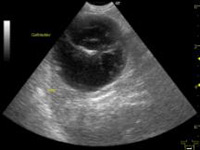

(pancreas=膵臓が腫大している)

超音波検査では、腫大した膵臓と膵臓周囲の腸間膜の輝度亢進、膵管の

拡張、腹水など診断に有用な所見が得られます。報告では、犬の急性膵炎の68%で超音波検査の異常があると示されています。